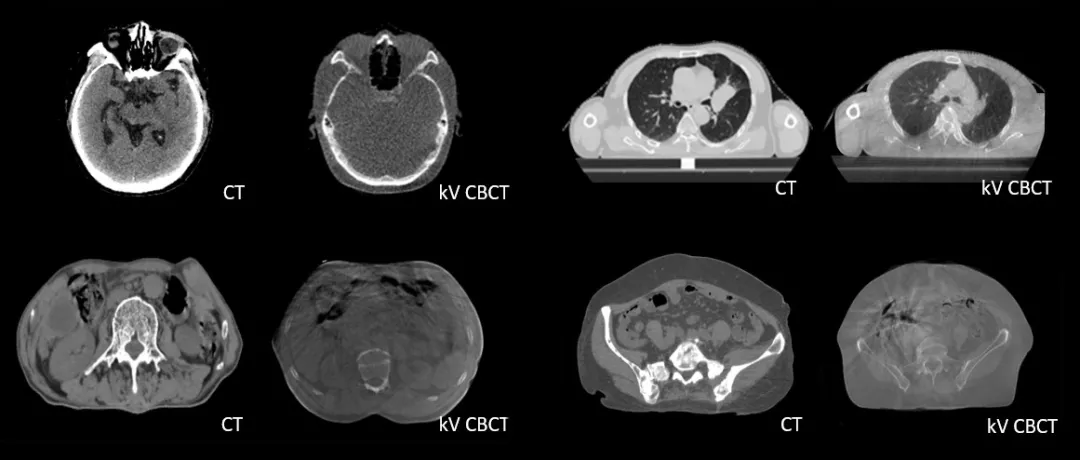

診斷級 CT對比kV-CBCT影像,更好地顯示器官和軟組織的邊界和細(xì)節(jié)